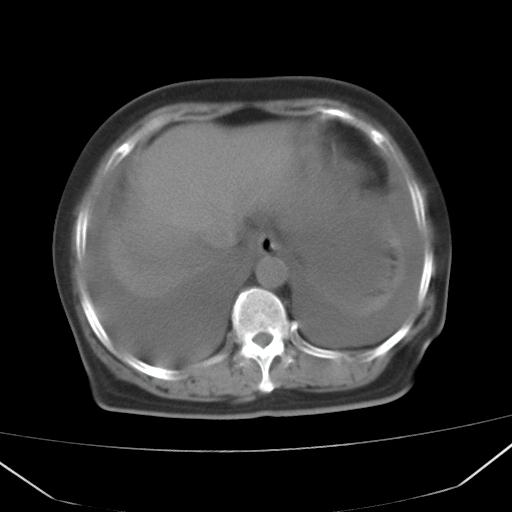

以下是引用jiangjing在2008-4-20 10:43:00的发言:[br]结合病史支持 冠心病[冠状动脉钙化],心功能不全,肺淤血、肺水肿,双侧胸腔与斜裂积液

以下是引用liuyue在2008-4-19 22:25:00的发言:[br]先考虑:1.心衰伴肺水肿、双侧胸腔积液、叶间积液、双下肺不完全性肺不张; [br] 2.冠状动脉粥样硬化。

以下是引用lijuanln在2008-4-19 23:05:00的发言:[br]两侧胸腔积液,肺水肿[br]心包积液[br]提示心衰